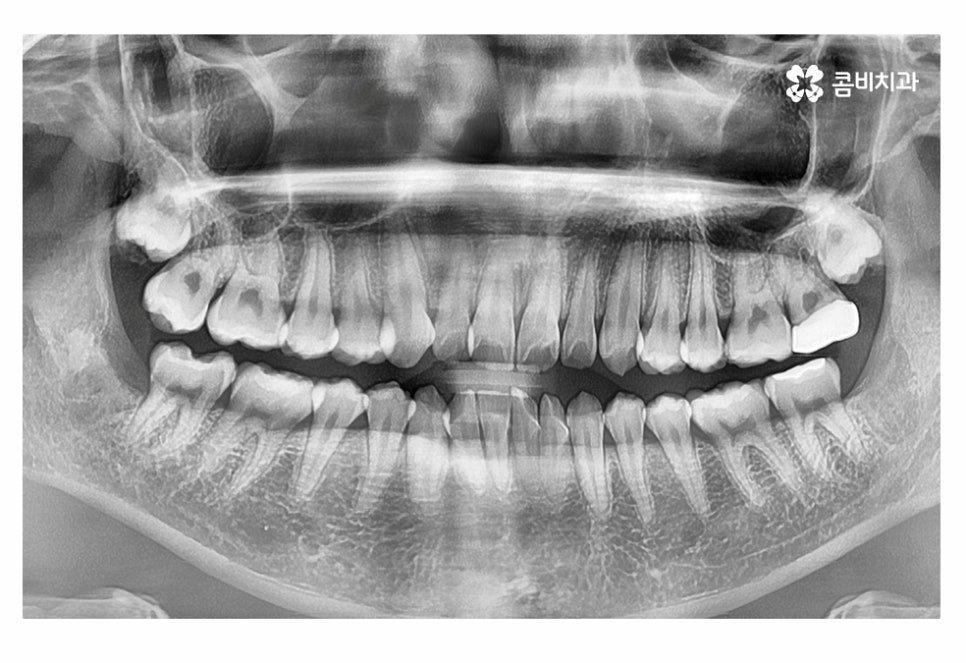

교합이 정상적이고 치아의 이동 공간을 고려할 때

치아부분교정이 가능했던 환자분이었기 때문에 윗니와 아랫니에

각각 부분교정이 진행된 사례라고 할 수 있는데요.

물론 치료 방법과 기간 등은 개개인의 치열과 골격 등을 정확하게

검진하고 판단해야 할 부분이지만 보편적으로 부분교정이

가능한 경우에는 전체 교정에 비해 기간, 비용, 관리 등의 장점이 있어요.